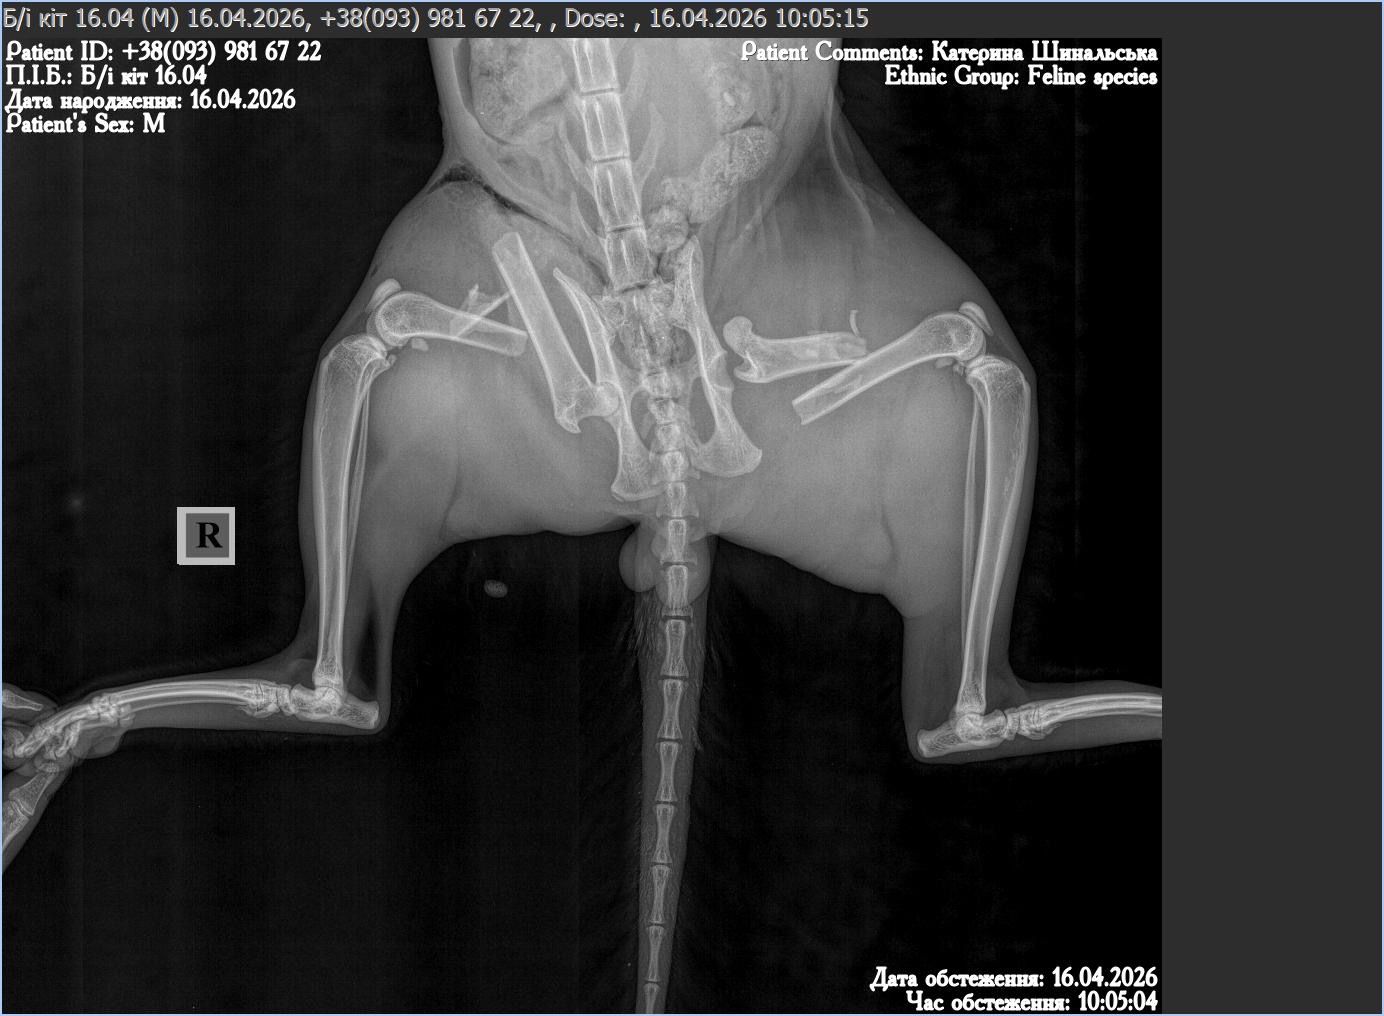

Droga gdzieś w Ukraina i on — małe ciało leżące nieruchomo. Nie ucieka, nie podnosi się, nawet nie próbuje. Obie tylne łapki złamane, biodro przemieszczone. Ciało, które jeszcze chwilę temu było szybkie i żywe, nagle przestaje działać.

Operacja jest długa i skomplikowana. W jego ciele zostaje specjalna konstrukcja, która ma utrzymać kości i dać im szansę się zrosnąć.